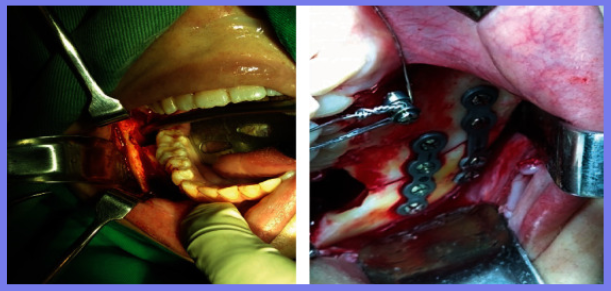

在医院对患者进行检查,除全身健康状况外,临床评估还显示右侧面部剧烈疼痛和肿胀、下颌轮廓明显凹陷、张口受限、咬合不正、前段骨性活动性差、右下颌第三磨牙缺失。计算机断层扫描 (CT) 扫描和 3D 重建分别显示直角部位下颌节段的牙槽骨连续性断裂和横向移位的髁突 (远端) 碎片。水肿消退后,在全身麻醉下进行下颌骨骨折治疗。外科医生进行口内切开复位,重新定位节段,并使用两块钛板和六毫米螺钉防止碎片移动并确保骨一期愈合。在同一手术中,对侧上下第三磨牙也被拔除。